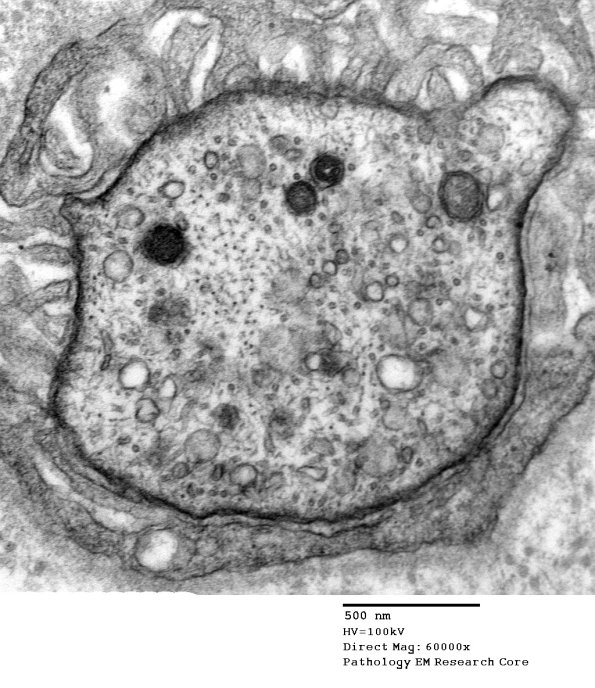

5A2 Node of Ranvier (Case 4, GBS) EM 021 - Copy

Higher magnification of image #5A1. (electron micrograph)